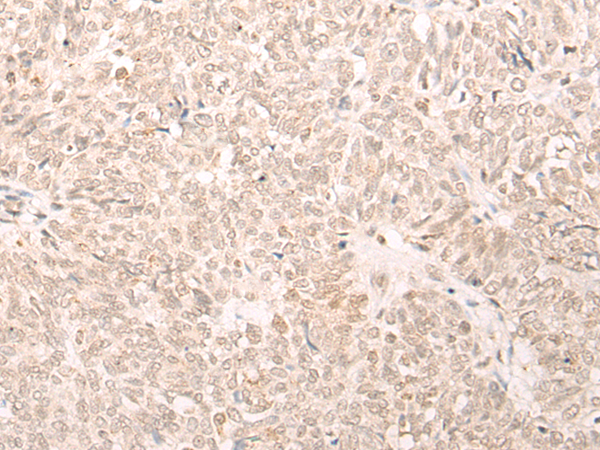

分类: 科研抗体货号: P06459别名: Fbx32; MAFbx应用: WB,IHC反应种属: Human, Mouse, Rat